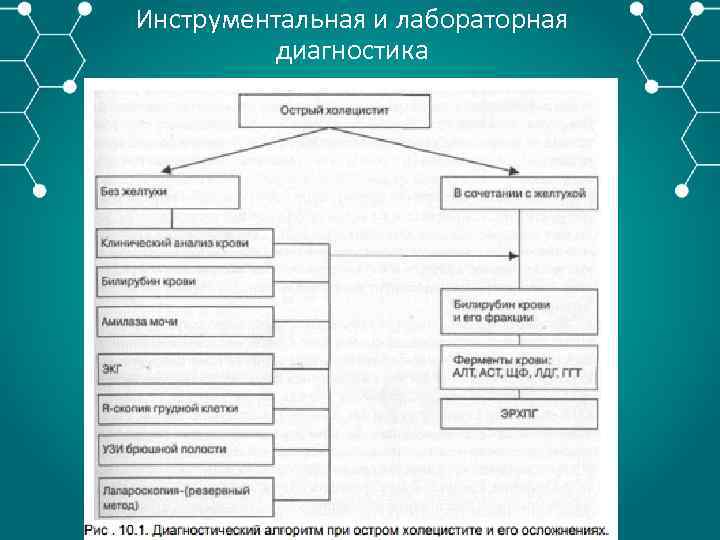

Инструментальная и лабораторная диагностика

Инструментальная и лабораторная диагностика ОАК – лейкоцитоз со сдвигом лейкоцитарной формулы влево. ОАМ – повышение кол ва амилазы. БХАК – повышение общего билирубина, ALT AST ЩФ СРБ. БХАК на амилазу, липазу, трипсин, эластазу повышение показателей и их активности выше нормы. УЗИ – признаки патологии желчного пузыря и желчевыводящих протоков. ЭРХПГ Рентгенография КТ Лапароскопия